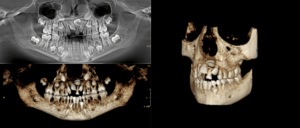

En nuestro Centro radiológico dental, contamos con equipamiento de vanguardia para ofrecerte los mejores resultados en radiografías dentales, radiografías panorámicas dentales, tomografía dental 3D y muchas más. Nuestro equipo de odontólogos está capacitado para brindarte la mejor atención para que tu dentista pueda tomar decisiones informadas sobre tu tratamiento. Además, nuestra radiología digital dental garantiza imágenes de alta calidad y reducción de daños por radiación. Si necesitas una radiografía panorámica dental, no dudes en visitarnos. Contáctanos para conocer nuestros precios y horarios de atención.